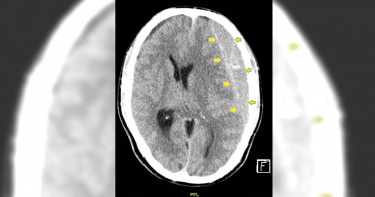

75歲施阿嬤身體硬朗,平時不僅下田耕種,還會爬樹收割龍眼,但她日前掃地時突然左側手腳癱軟無力,機警女兒發現趕緊撥打119求救,經現場評估,研判是腦中風引起,立即聯絡醫院緊急應變,到院後先經靜脈注射血栓溶解劑,隨後又在30分鐘內完成顱內取拴術打通血管,讓她重溫含飴弄孫之樂。及時撥打119 啟動腦中風團隊霧峰消防隊救護人員抵達現場後,根據患者癱瘓狀況及臉部歪斜表情,懷疑是大血管阻塞引起的急性腦中風。立即以台中市特有的到院前五級檢傷預通報系統,通知亞洲大學附屬醫院準備,院方接獲訊息後,立即啟動腦中風團隊,並請放射科同仁空出電腦斷層室。患者到院後,立即安排腦部電腦斷層檢查。團隊檢視影像後確認為右側中大腦動脈第1-2段交界處阻塞,且無腦內出血狀況,除了施行血栓溶解劑治療,並立即安排顱內動脈取拴術,搶救缺血但尚未壞死的腦部。打通取出血栓 解除危及警報放射診斷科宋昌育醫師表示,先從患者鼠膝部置入導管,透過由粗到細的同軸套疊方式,經腹部、胸腔主動脈及頸部動脈直達阻塞的腦動脈區,再以導管抽吸方式,將血栓取出清除打通血管,「很幸運阿嬤的血管沒有太過扭曲,幾乎一路順暢直達」,才能順利在30分鐘內取出血栓,安全解除警報。把握黃金時間 以利預後恢復較佳生活品質神經內科吳致螢醫師也表示,缺血性腦中風往往會造成嚴重的神經學損傷甚至死亡,處理腦中風患者最重要的關鍵,就是「黃金時間」,例如發生3小時內及時施打靜脈血栓溶解劑,若效果不佳,也要在中風發生8小時內安排動脈取栓,都有助於患者預後可恢復較佳生活品質。

北部一名60歲婦人不菸不酒、不下廚、勤運動,最近1、2個月因左側突然沒力懷疑是中風,經確診為肺腺癌「腫瘤還轉移到腦部」,讓她無法接受,對此,醫師也坦言,臨床上見到太多無症狀的肺癌患者「自己都會害怕」。北部一名60歲婦人不菸不酒、不下廚、勤運動,最近1、2個月因左側突然沒力懷疑是中風。胸腔內科醫師徐培菘在《醫師好辣》節目中分享,這名60歲婦人一開始因左側突然癱軟無力狀況頻繁,於是找上神經科名醫照電腦斷層,豈料驚見一顆「別的地方轉移來的」腦部腫瘤,轉介至胸腔科進一步檢查,發現肺部冒出2公分腫瘤,確診肺腺癌轉移腦部,才會導致肢體無力。婦人轉介至胸腔科進一步檢查,發現肺部冒出2公分腫瘤,確診肺腺癌轉移腦部,才會導致肢體無力。這如同晴天霹靂的消息讓婦人難以接受,這名患者本身不菸不酒、也不煮飯、規律運動又養生,難以接受「會得到這疾病」。對此,徐培菘解釋,肺腺癌好發位置在於肺部周邊,不會壓迫到氣管因此鮮少出現症狀,甚至有腫瘤已經暴長4、5公分的患者說「都沒症狀、沒感覺」。徐培菘表示,肺癌危險因子最常見就是抽菸和廚房油煙。根據徐培菘表示,肺癌危險因子最常見就是抽菸和廚房油煙,尤其中式料理大油熱炒,建議在家中料理時,可以將空氣清淨機在油煙特別大時打開,會發現此時的PM2.5超高。另外,他呼籲居家環境或工作場合裡的危險因子也要留意,特別是被WHO認定為第一級致癌物的空氣汙染PM2.5難以避免,出門時也應妥善戴好口罩,降低罹癌風險。若要及早發現症狀,徐培菘建議,可進行目前被認為唯一能揪出早期肺癌的「低劑量肺部電腦斷層」,經追蹤若被判定有風險可考慮手術切除,尤其是長期一天一包菸抽30年或一天2包菸抽15年的老菸槍、年紀超過40歲者、以及三等親內有家族史者都應該做,而徐培菘也坦言,自己會做這項檢查,原因是「看到太多沒症狀的(罹癌患者),自己都還是會害怕」。

近期天氣變化大,彰化基督教醫院就發現,腦出血性中風患者比去年同期多4成,日前就有一名患者感到頭部劇烈疼痛,隨後出現四肢癱軟、意識模糊的狀況,送醫後更是呈現重度昏迷,也讓醫師提醒,慢性病患者一定要留意身體狀況,並學會保命4招,若發生疑似症狀,一定要趕緊處置並送醫。一名患者聊天到一半感到頭痛欲裂,隨後四肢癱軟昏迷,沒想到就是腦出血性中風。(示意圖/翻攝自unsplash)彰化基督教醫院近日表示,近期有一名50歲左右的患者,在和家人聊天期間,突然感到頭痛、噁心想吐,接著更是出現四肢癱軟無力、意識模糊的狀況,家人趕緊將他送醫,到院時已呈現重度昏迷的狀況,檢查後發現他的腦部血管瘤破裂,加上本身又有高血壓,只能立刻緊急手術搶救。經過搶救後,患者成功撿回一命,但也讓人擔心腦出血性中風的影響,彰化基督教醫院神經醫學部主治醫師陳彥中就表示,可以透過4口訣來快速辨識腦中風症狀與保命。4口訣牢記,千萬不要耽誤了黃金治療時間。(示意圖/翻攝自unsplash)「手」指的是雙手平舉,看有沒有單側瞬間無力狀況發生;「嘴」則是照鏡子並觀察嘴巴有沒有歪斜現象;「說」跟別人對談時,是否有口齒不清、表達不清楚的狀況。若發生以上的3種現象,就要「快」,盡快打119或送至急診室。

黎先生是位年輕、身強體健的外籍移工,一天在工作時,突然間劇烈頭痛合併右側的肢體癱軟無力,在朋友的陪伴下來到亞東醫院急診室,經急診范副主任評估後,安排電腦斷層檢查發覺腦部異常,遂委請神經外科岑昇信醫師診療。經評估後確定為頭部慢性硬腦膜下血腫合併急性出血,幸而緊急開刀後順利的康復,黎先生恢復了原有的笑容。岑昇信醫師表示,患者往往因為血腫的壓力造成腦壓增加及神經壓迫而出現肢體無力、意識改變的問題,需要緊急手術將血腫清除,以免腦部神經因為長時間被擠壓而造成無法挽回的傷害。急性硬腦膜下血腫大部分伴隨明顯頭部外傷的病史,而且症狀來得又快又猛;而慢性硬腦膜下血腫往往沒有明顯的外傷病史,臨床上症狀惡化較緩慢、較不明顯。症狀不明顯的慢性硬腦膜下血腫的病人,在沒有外傷的情況底下出現急性出血,對病人的影響也會來的非常快,硬腦膜下血腫造成神經壓迫及腦壓增加,造成病人出現肢體無力、意識改變等問題,黎先生就是這樣的個案。岑昇信醫師回憶,黎先生因為剛來台灣不久,無法用中文溝通,感謝現在的科技發達,手機翻譯軟體能協助醫師與病人溝通,若內容太複雜,就勞煩病房的越南籍看護大姊充當翻譯。經過充分溝通、解釋病況,黎先生順利在手術後一週順利康復出院,在積極復健治療之下,手腳也力量很快就恢復。回診時,岑醫師再度利用翻譯軟體的便利,仔細叮囑後續的一些注意事項。並非所有的腦部手術病人都可以恢復良好、不留下後遺症,即時送醫治療、仰賴團隊合作、快速診斷、準確治療,才能儘量減少病人神經損傷,並在後續自身積極復健,都是能否復原的重要因素。岑昇信醫師呼籲,如果有任何外傷導致出現急性病徵,一定要盡快就醫,才能在黃金時間內做出最好的診治,後續配合醫師指示進行復建,才能將對身體的傷害降到最低。